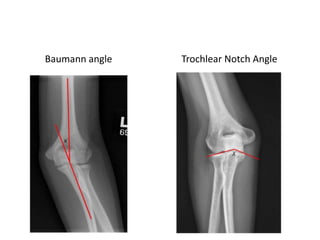

Measurements on AP radiograph

1. Radial Neck- Shaft Angle

2. Articular Surface Angle

3. Carrying Angle

4. The Baumann angle

5. Trochlear Notch Angle

6. Articular Surface Assessment

Baumann angle Trochlear Notch Angle